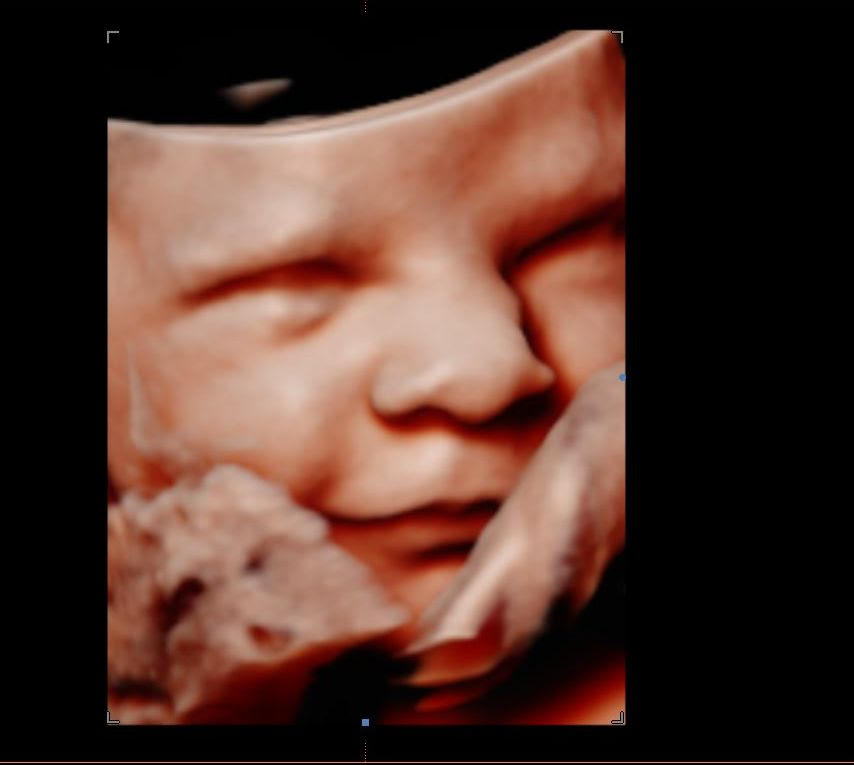

Browsing our 4D ultrasound photos gives you a clear idea of what your session can look like. You will see a range of images, from early 2D visits and gender reveal moments to rich 3D, 4D, and HD live facial detail captured during the most popular weeks between 26 and 32 weeks. Babies are unpredictable, but we have spent many sessions helping families get those sweet expressions, tiny stretched arms, and peaceful faces that you will want to hold onto for years.

Your session at Behind the Bump HD begins with your comfort. We start with 2D imaging to locate baby and find the best viewing angle, then move into 3D, 4D, and HD live ultrasound when position allows. Most visits last between 10 and 25 minutes of scanning time depending on your chosen package, and we take the time to try different positions and techniques to capture the clearest possible views.

Image clarity depends on factors like baby’s position, amniotic fluid levels, and gestational age. If your heart is set on detailed facial images, booking between 26 and 32 weeks gives you the best chance of seeing those fuller features and that characteristic stillness babies often have later in pregnancy.